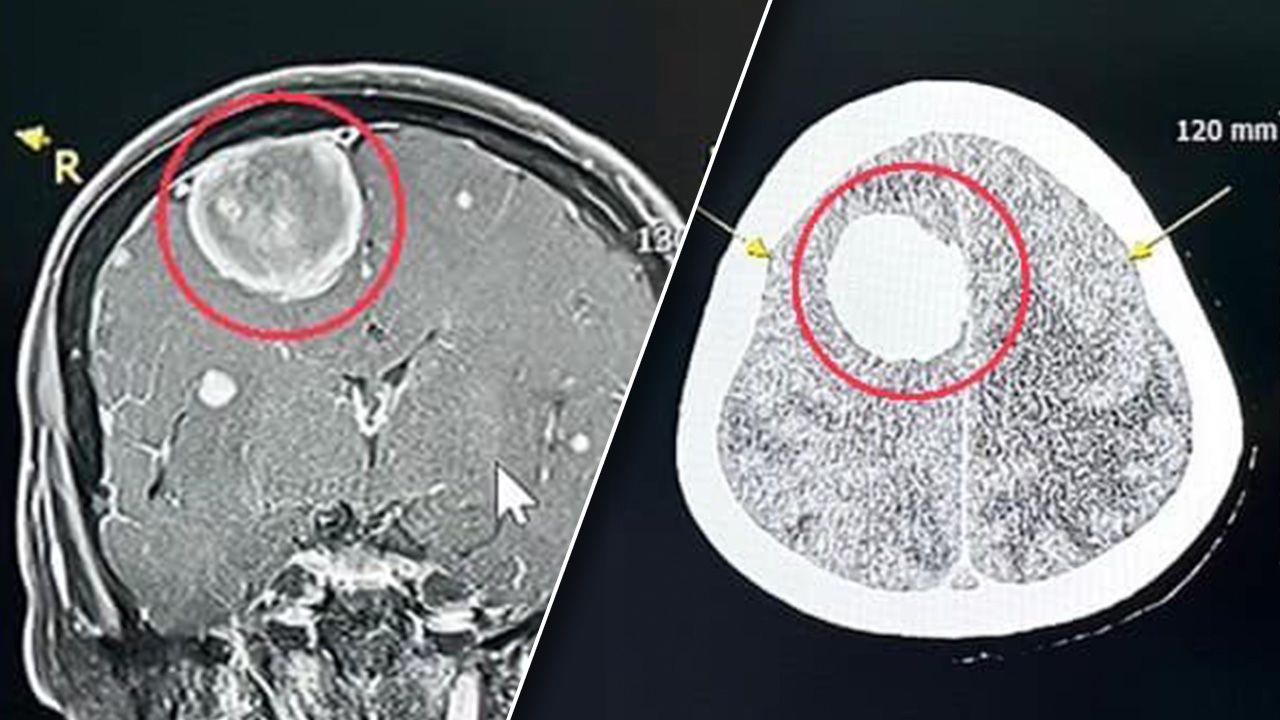

แพทย์เวรตรวจเบื้องต้น สงสัยอาการทางสมอง จึงส่งตรวจคลื่นแม่เหล็กไฟฟ้าสมอง พบเนื้องอกในสมองขนาด 3 เซนติเมตร จึงแนะนำให้นอนโรงพยาบาล วางแผนผ่าตัด ส่งปรึกษาแพทย์ผู้เชี่ยวชาญด้านประสาทศัลยศาสตร์ นัดผ่าตัดสมอง เอาก้อนเนื้อออกมาเป็นผลสำเร็จ โดยไม่มีผลต่อการทำลายเนื้อสมอง สามารถผ่าเอาเนื้องอกออกมาได้ทั้งก้อน